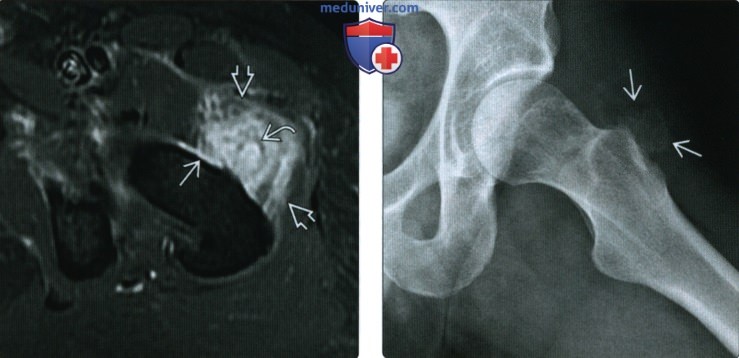

Оссификация тазобедренных суставов: что это и как проявляется?